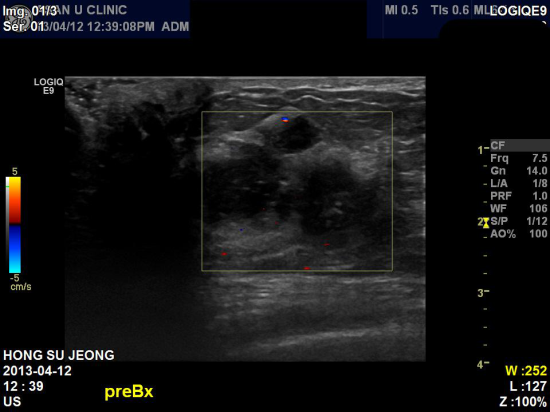

상기환자 우측 유방 통증은 없으나, 만져지는 멍우리로 내원하신 52세 여성분이십니다.

본원 초음파상 우측 유방 2.95cm 미세석회화 소견 보여

조직검사 시행하였으며, 유방암으로 진단되었습니다.